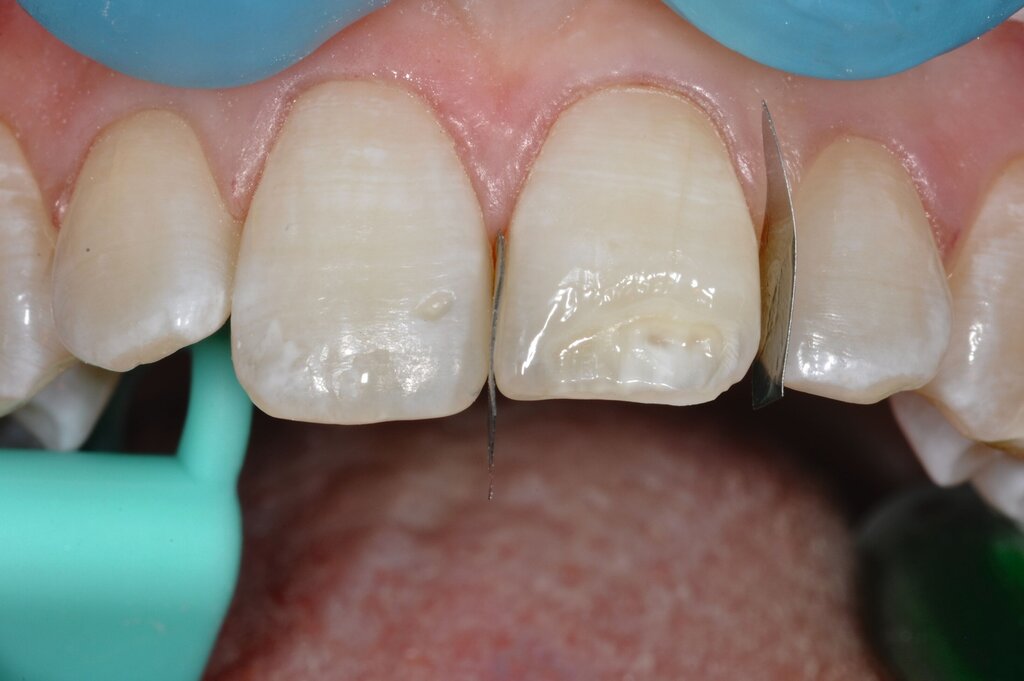

Die direkte Versorgung mit Komposit hat den Vorteil, dass durch die Verwendung von Dentinadhäsiven das Dentin dicht versiegelt werden kann. Hypersensitivitäten werden dadurch deutlich reduziert. Zudem kann der Zahn bei der direkten Versorgung sehr defektorientiert versorgt werden (Abbildung 7).

Während die Dentinhaftung unterhalb des affektierten Schmelzes vergleichbar mit der von gesundem Dentin ist, funktioniert die Haftung an dem strukturell veränderten Schmelz schlechter. Eigene Untersuchungen haben gezeigt, dass die Haftung an dem porösen, proteinreichen Schmelz stark reduziert ist (Abbildung 8) [Krämer et al., 2018]. Sind die Füllungsränder in dem veränderten Bereich lokalisiert, muss mit Randspalten und Abplatzungen gerechnet werden.

Bei größeren Restaurationen muss man im Laufe der Jahre mit Verfärbungen der Füllungen und mit Abrasionen rechnen. Dies spielt insbesondere eine Rolle, wenn im Seitenzahnbereich Höcker ersetzt werden müssen, da Kompositfüllungen mit Höckerersatz an MIH-Molaren eine etwas geringere durchschnittliche Überlebenszeit in der Mundhöhle haben als solche ohne Höckerrekonstruktion [Rolim et al., 2021].